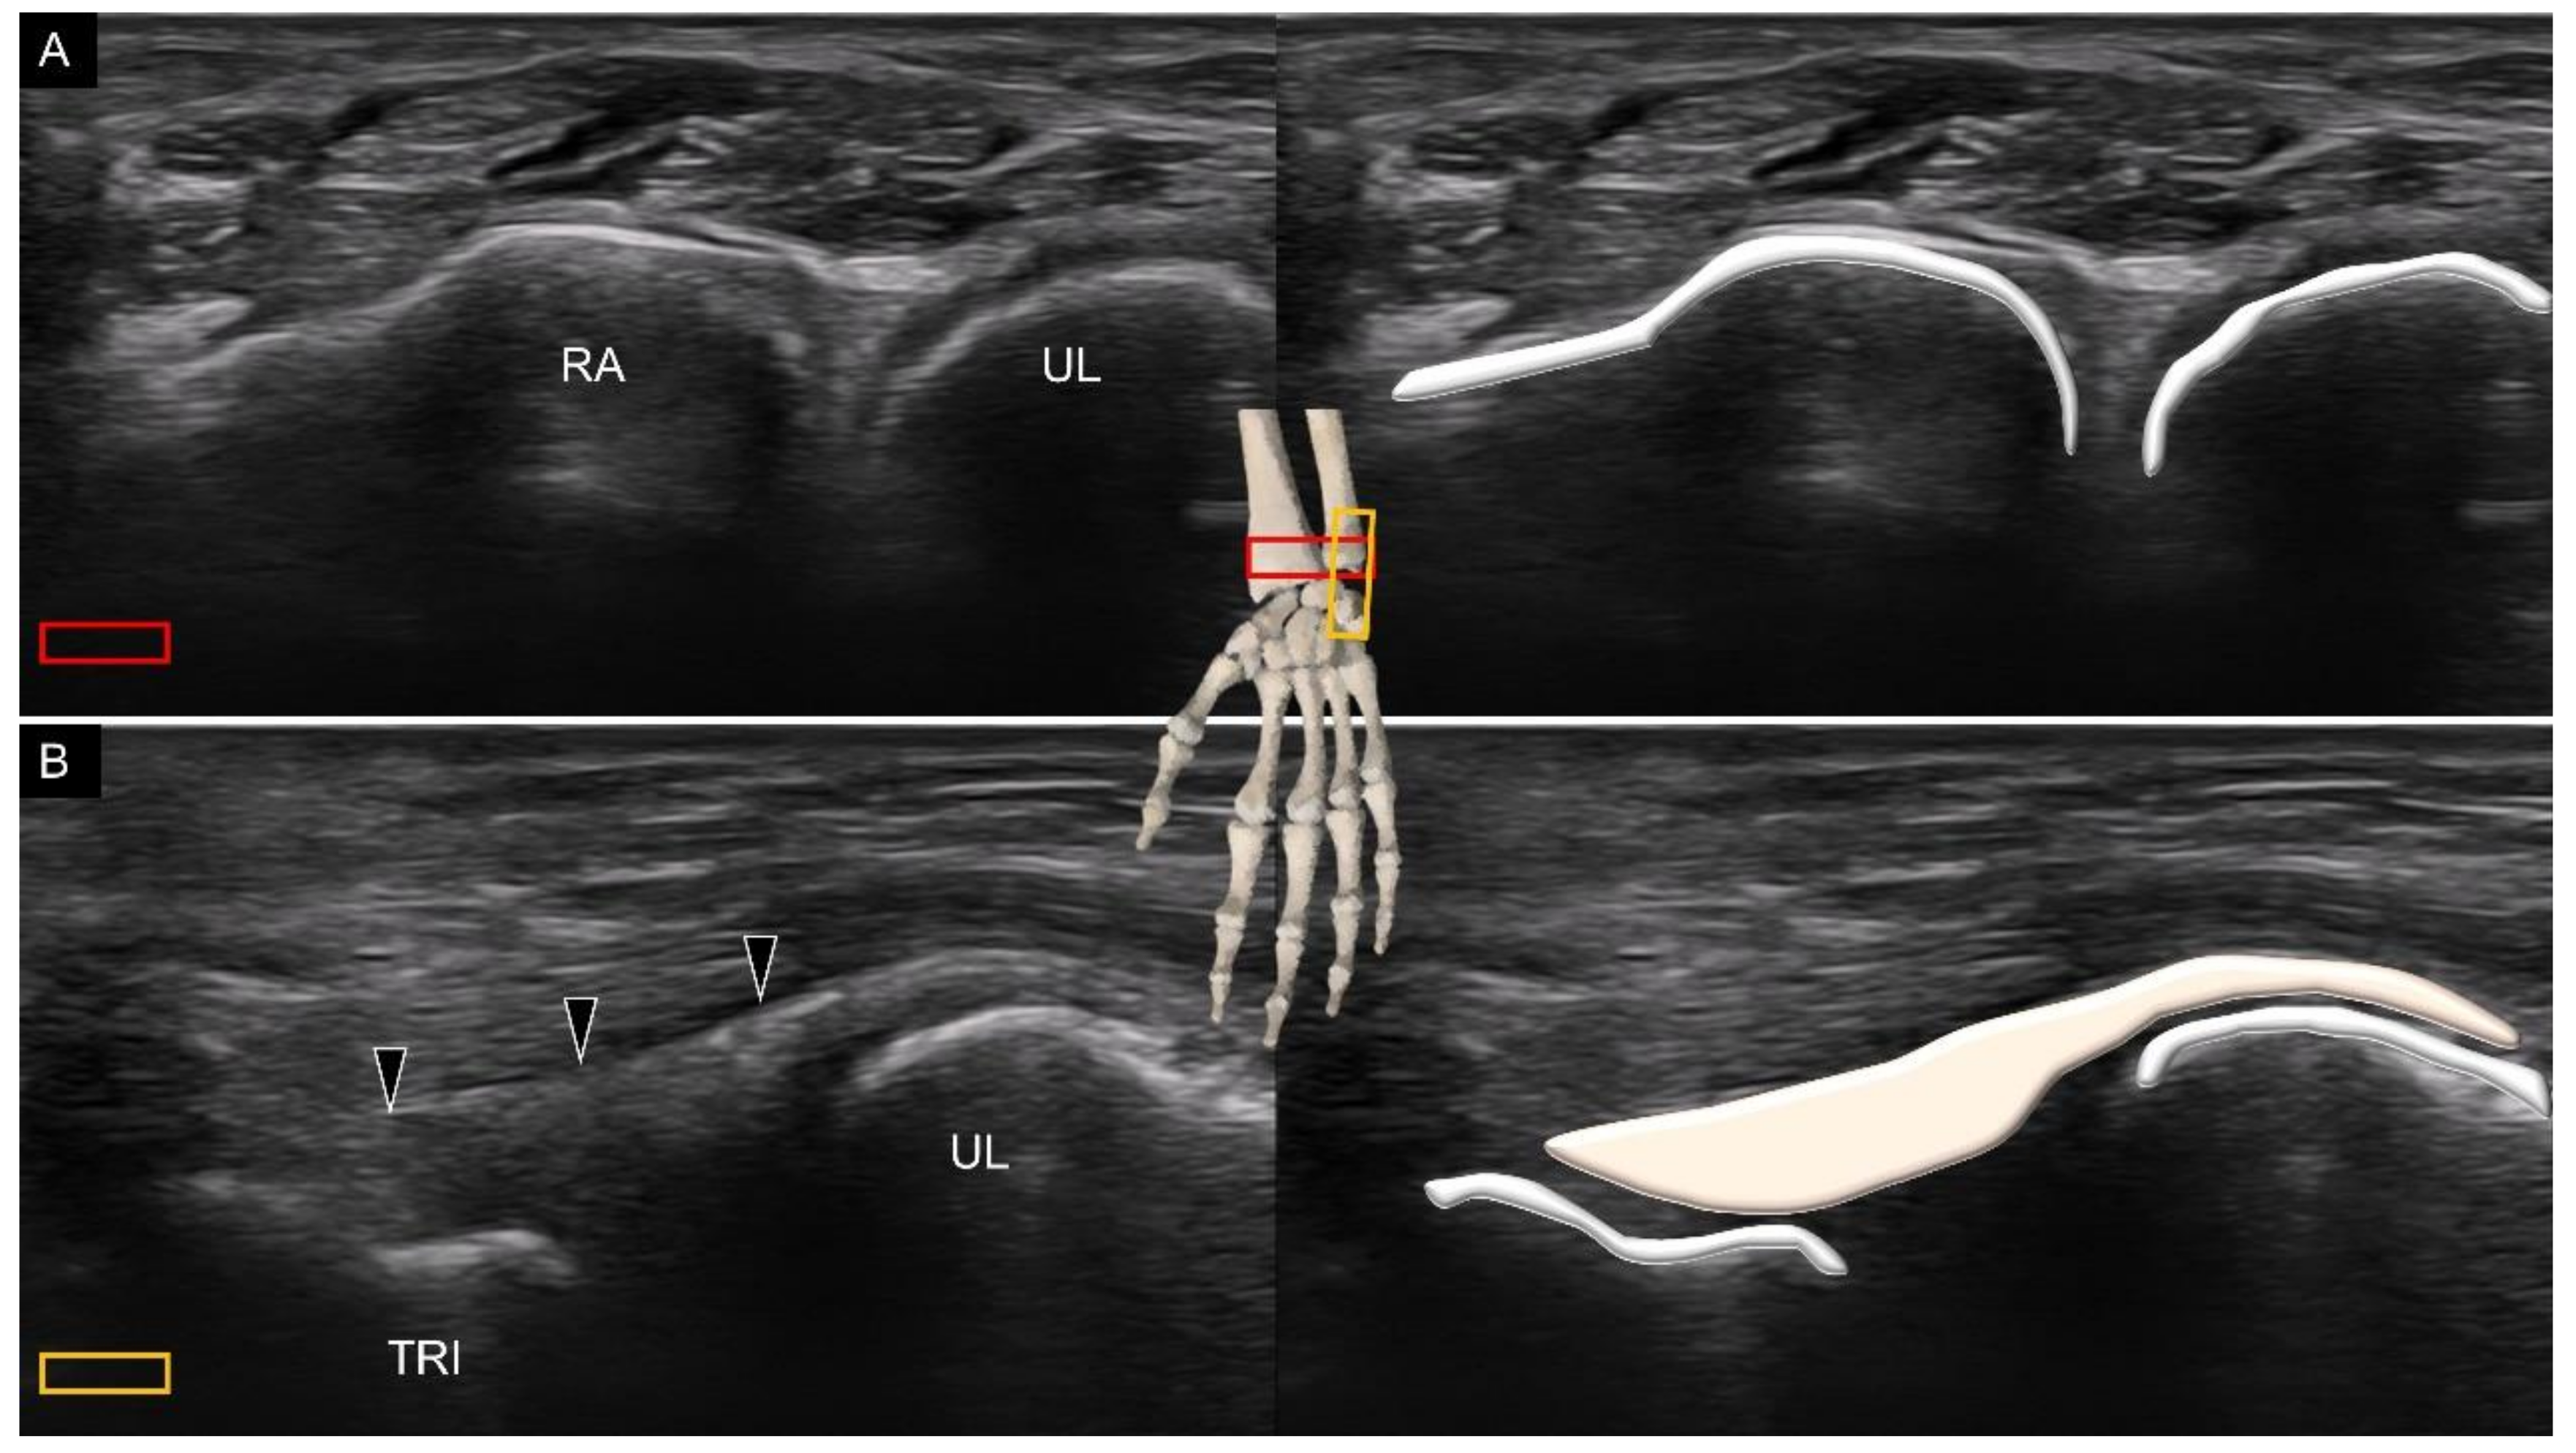

7. Sonoanatomy of Wrist Collateral Ligaments